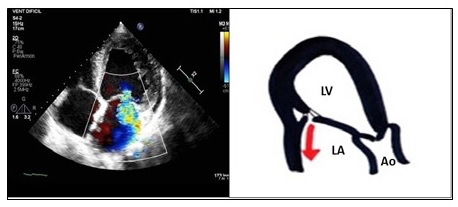

The symmetric closure is due to a global remodelling of the LV, with a spheroidal shape and greater dysfunction. There is an apical displacement of both leaflets and the coaptation point, with greater dilation and flattening of the mitral annulus. The area and volume of tenting are greater than in the asymmetric pattern, being the origin and direction of the central regurgitation jet, by a symmetrical effect on both leaflets. It is associated more with anterior infarction or multiple infarcts (Figure 2).

Figure 2. An apical three-chamber view, showing ischaemic mitral regurgitation with symmetrical closure: this is due to a global remodelling of the left ventricle, with apical displacement of both leaflets and the coaptation point. The insufficiency jet is central, due to a symmetrical effect on both leaflets. Echocardiographic image on the left and schematic drawing on the right.

Ao: aorta; LA: left atrium; LV: left ventricle